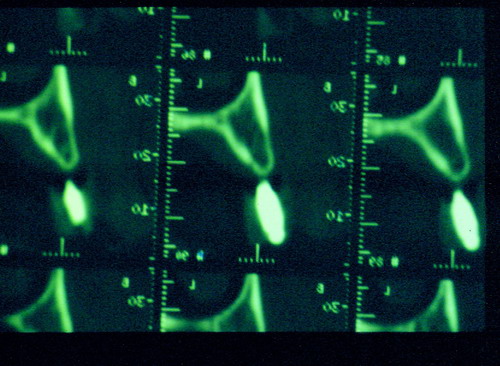

LA OCLUSIÓN MUTUAMENTE PROTEGIDA ES UN VIEJO CONCEPTO QUE CONSISTE EN LA MUTUA INTERACCIÓN DE LOS DISTINTOS GRUPOS DENTARIOS ENTRE SI. DE ESTA FORMA, LA TABLA PREMOLAR / MOLAR DE AMBOS HEMIMAXILARES ANTAGONISTAS, DETIENEN EL CIERRE MANDIBULAR EN CÉNTRICA, LOS CANINOS DISCLUYEN LAS PIEZAS POSTERIORES DURANTE LAS TRANSTRUSIONES, Y EL GRUPO INCISIVO LO MISMO DURANTE LAS PROPULSIVAS. SIN EMBARGO, DICHO CONCEPTO ES LIMITADO A LAS PIEZAS DENTARIAS, SIN TENER EN CONSIDERACIÓN LA IMPORTANTE FUNCIÓN QUE RECAE SOBRE LA ATM Y EN EL SOPORTE DE PRESIONES DURANTE ESTA DINÁMICA. ES ASI QUE EN EL AÑO 1981, EL DR. ANIBAL ALONSO GENERA EN LA CIUDAD DE BUENOS AIRES UN CONCEPTO MAS AMPLIO QUE DENOMINÓ : OCLUSION MUTUAMENTE COMPARTIDA. REF I EN EL QUE AMPLÍA EL CONCEPTO ANTERIOR, HACIENDO PARTÍCIPE A LA ATM EN LA MISMA. CUANDO EXISTE CARENCIA DE PIEZAS DENTARIAS POSTERIORES, YA SEA DE UN SOLO LADO O DE AMBOS , EL CIERRE MANDIBULAR ES DETENIDO POR LAS PIEZAS RESTANTE, FORZANDO A LA ATM A SOPORTAR PRESIONES MUY SUPERIORES A AQUELLAS PARA LAS QUE ESTA PREPARADA. FIG1 FIG2 FIG3 LUEGO DEL ESTUDIO CLÍNICO DE RIGOR, DONDE SE EVALÚA RADIOGRÁFICA Y PERIODONTALMENTE, SE PROCEDE A TOMAR MODELOS DE ESTUDIO Y MONTAR EN ARTICULADOR SEMIAJUSTABLE, SOBRE EL CUAL SE REALIZA UN ENCERADO PROGRESIVO DE DIAGNÓSTICO, A PARTIR DEL CUAL SE CONFECCIONA UN JUEGO COMPLETO DE PROVISIONALES DE AMBAS ARCADAS , INCLUYENDO LAS PIEZAS FALTANTES. SE ABORDA EL CASO YA QUIRÚRGICAMENTE DONDE EN UNA PRIMERA ETAPA SE TALLAN PRIMARIAMENTE LAS PIEZAS DENTARIAS Y SE PROCEDE, EXODONCIANDO EL INCISIVO CENTRAL SUPERIOR DERECHO, A REALIZAR UNA ROG(REGENERACIÓN ÓSEA GUIADA), PARA INMEDIATAMENTE INSTALAR PARTE DE NUESTROS PROVISORIOS EN LA GUIA ANTERIOR. SE ADAPTAN A LOS SECTORES POSTERIORES LAS PRÓTESIS REMOVIBLES QUE PORTABA, Y SE ESPERAN CUATRO MESES, AL CABO DE LOS CUALES SE REALIZA UN ESTUDIO CON DENTASCAN, MEDIANTE EL USO DE UNA FÉRULA RADIOLÓGICA CON TUBOS METÁLICOS , QUE NOS SERVIRÁ TAMBIÉN DE GUÍA QUIRÚRGICA. PROCEDEMOS ENTONCES A LA IMPLANTACIÓN DE LOS SECTORES EDÉNTULOS MEDIANTE IMPLANTES ROSCADOS Y TÉCNICA SEMI SUMERGIDA. TRANSCURRIDAS OCHO SEMANAS OBSERVAMOS UNA CORRECTA SALUD PERIMPLANTARIA, Y REALIZAMOS LA INSTALACIÓN DE LOS ABUTTMENTS ALCANZAMOS ENTONCES EL PUNTO EXACTO DONDE DEBEREMOS COMENZAR A RECONTRUIR EN FORMA PERMANENTE. PAZ DEL SISTEMA: CENTRICIDADARTICULAR-PAZ MUSCULAR-ESTABILIDAD- -ACOPLAMIENTO. BASES FUNDAMENTALES DE LA OCLUSIÓN ORGÁNICA FIG41 FIG42 PROCEDEMOS NUEVAMENTE A TOMAR IMPRESIONES, EN ESTE CASO DEFINITIVAS , MONTAR NUEVAMENTE EN ARTICULADOR, Y CONSTRUIR LAS RESTAURACIONES PERIFÉRICAS TOTALES EN BASE A PORCELANA SOBRE ORO GALVANIZADO. REF. II SOBRE LAS MISMAS TERMINADAS Y YA EN BOCA, CHEQUEÁMOS TODOS LOS ELEMENTOS QUE CONSTITUYEN UNA REHABILITACIÓN ORAL INTEGRAL, DESDE LA SALUD ENDODONTICA DE PIEZAS TRATADAS O NO, LA SALUD PERIODONTAL, EL AJUSTE PERIFÉRICO DE LAS RESTAURACIONES, LA ESTABILIDAD EN LA ATM, Y LAS FUNCIONES OCLUSALES, CHEQUEOS ESTOS QUE SE REPETIRAN EN CADA UNO DE LOS CONTROLES POST OPERATORIOS. FIG46 FIG47 FIG48 FIG66 FIG67 REFERENCIAS: REF I: OCLUSIÓN Y DIAGNÓSTICO EN REHABILITACIÓN ORAL REF. II ELECTROFORMACIÓN EN ODONTOLOGÍA RESTAURADORA.